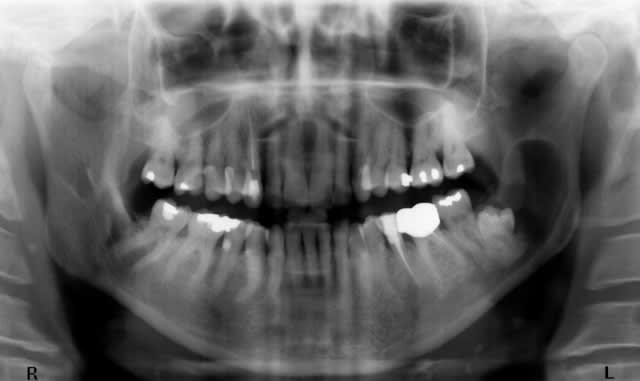

Quel âge a le patient ? et quelles sont les circonstances de découverte ? infection, fortuit ?

Pour l'AG je crois que j'ai ma réponse car sur la vue endibuccale pré-op il me semble qu'il y a un morceau du packing visible qui déborde l'écarteur.

- non je n'ai pas encore l'anapath mais vu la lésion monogéodique uniloculaire, il s'agit à 99% d'un kyste péricoronaire de la DDS.